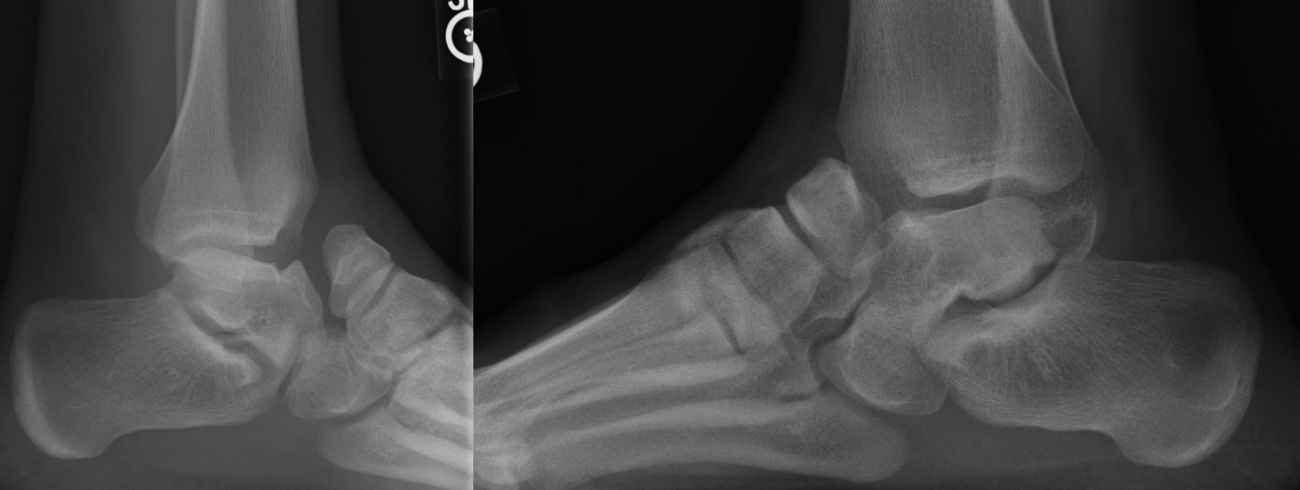

So, to summarize, true congenital clubfeet have abnormal talar bodies, which lead to abnormal ankle and subtalar joints with short Achilles and tight posterior tibial tendons. Regardless of treatment, there is nothing anyone can do to make the talus a normal bone. Many of these cases can and will develop additional deformities. Only the Cincinnati release can address every issue associated with the deformity, but it is NOT a cure. The Ponseti procedure is a total compromise, also NOT a cure. The sooner everyone treats the Ponseti as a compromise, I believe we will be far happier with the outcomes. I remember discussing this with others treating pediatric orthopedic issues during the rise of the Ponseti in the early 2000s. We all agreed, undercorrecting the deformity will lead to more surgeries and residual deformities. Until we all face the reality that clubfeet are a genetic deformity and not just a positional deformity, we will never make them perfect. Thus, athletes and the military will put any and all clubfeet patients to the test. There is no doubt that exceptions exist, but in time, at least based on our limited review of over 1000 clubfeet and 250 cases we saw in the military, no one is immune to complications, arthritis, and ultimately disability.

Here is a typical case presentation. A 21-year-old Marine at Ft. Leonard Wood for training underwent a Cincinnati release at one year old and had stellar follow-up. Her surgeon even wrote her medical waiver for entrance into the Marines. She ran track in high school. She finished boot camp and completed all of her Marine training, but now has chronic pain. She no longer can run. She hasn’t passed her physical training in over a year. She developed talonavicular DJD. By all accounts, her overall clubfoot should be rated an A+; no residual deformity, normal talocalcaneal angles on AP and lateral views, no equinus, no residual varus, only slight met primus elevatus, but no signs of a flattop talus. Clinically, she lacks subtalar range of motion, which I commonly find post-clubfoot release of any kind. So many in the military do very well for a while, but the demands of the military eventually catch up to them. We all root for clubfeet to make it, but the odds are stacked against them.